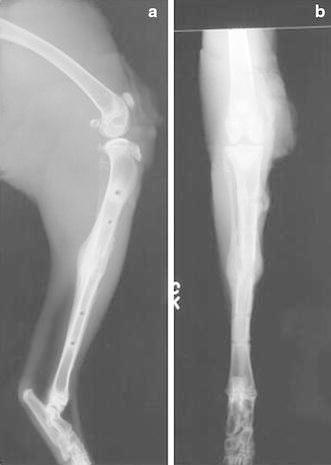

Animals in both arms of the study were euthanized. At 16 weeks of age, the right hind limb was disarticulated and aligned to produce consistent craniocaudal and mediolateral images with a Siemens (Erlangen, Germany) Multix H/UPH configuration with a focus to film distance of 100 cm and a 50-kV (±2 mV) and 4-mA exposure (Fig. 3). A single observer (FPM) assessed regenerate length, AP, and lateral alignment on the orthogonal images.

Fig. 3.

a Lateral and b AP radiographs of the tibia after removal of the fixator. Note the elliptical callus formation, the limb alignment, and the distance between the osteotomy and the pin sites